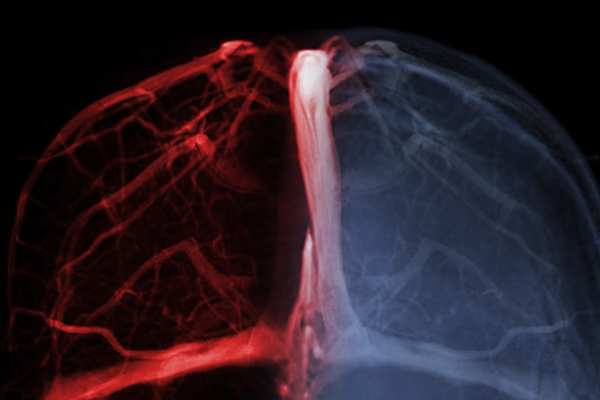

- MR Anjiyografi